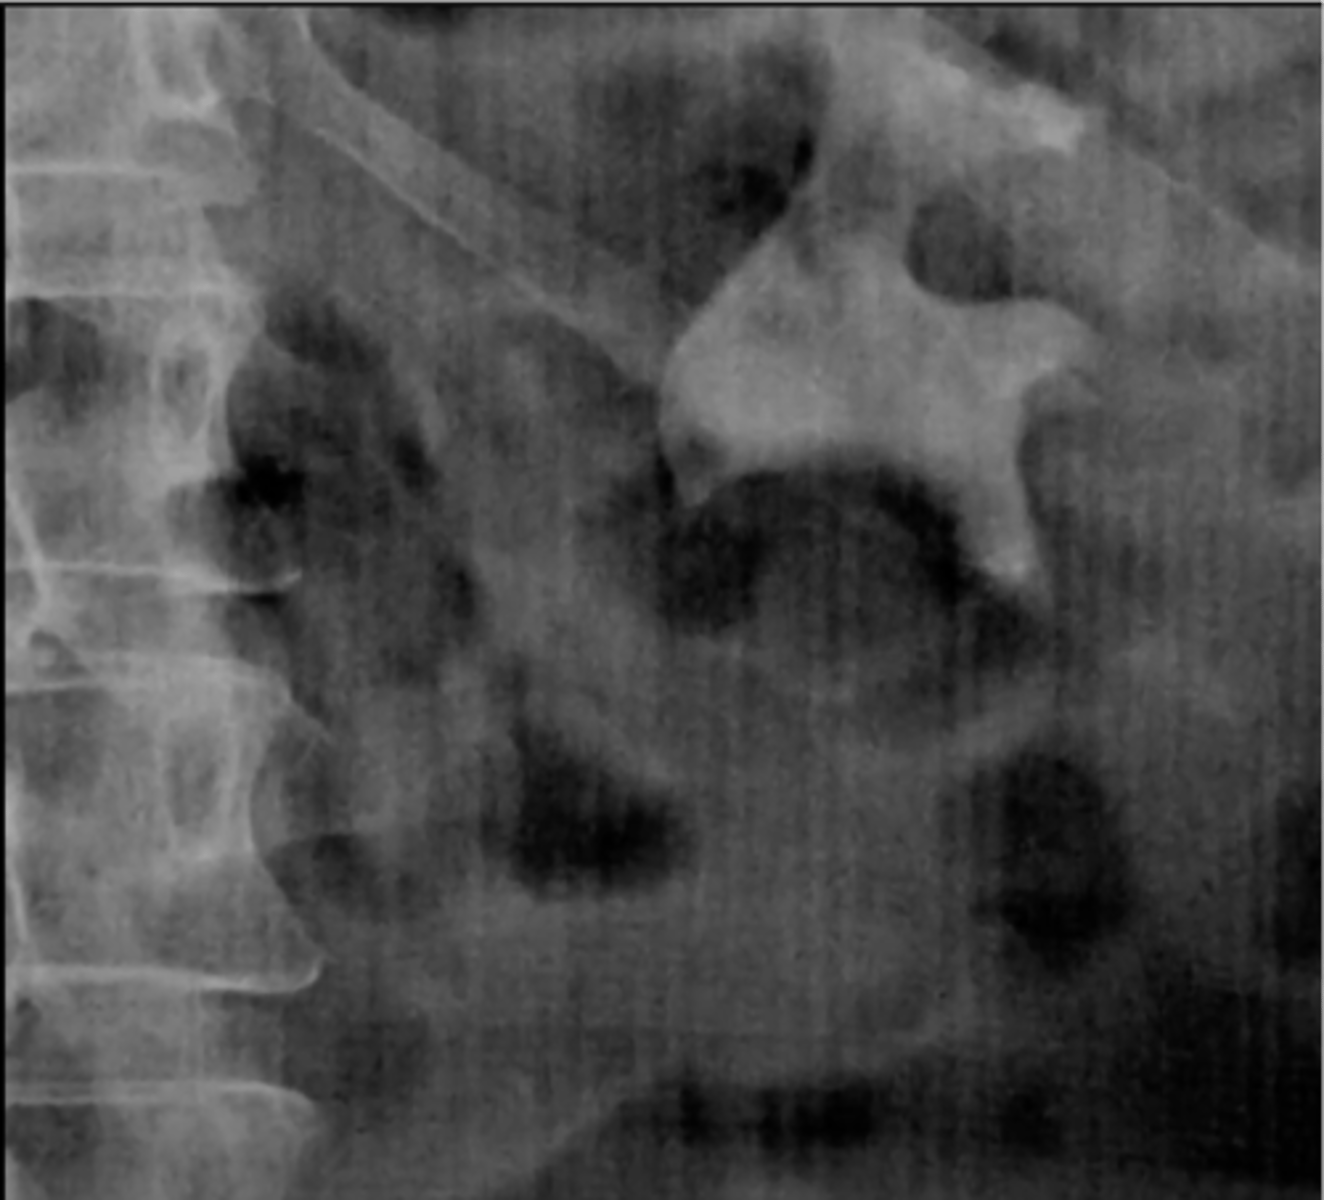

Large bowel haustra (pic 2)

Small bowel (Valvulae conniventes)